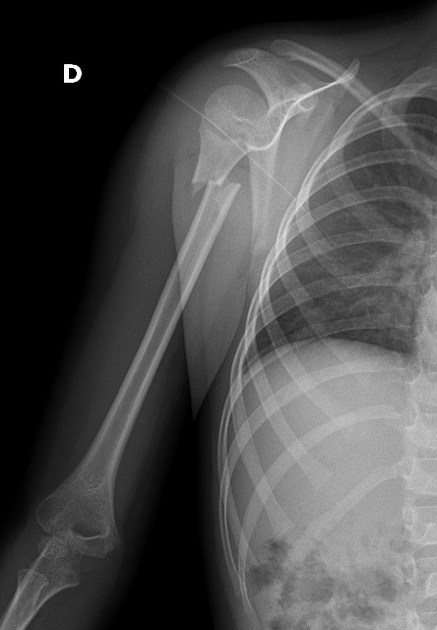

⚡Проксимальный перелом плечевой кости⚡

Данные Пациента Возраст: 6 лет Пол: Женский ❗❗Такие переломы достаточно редкие в данном возрасте ❗❗ Обычно переломы такого типа лечат консервативно. Переломы в проксимальной части плеча могут сочетаться с вывихом в плечевом суставе, особенно у детей. #ргснимок

❗❗Такие переломы достаточно редкие в данном возрасте ❗❗

Обычно переломы такого типа лечат консервативно.

Переломы в проксимальной части плеча могут сочетаться с вывихом в плечевом суставе, особенно у детей.